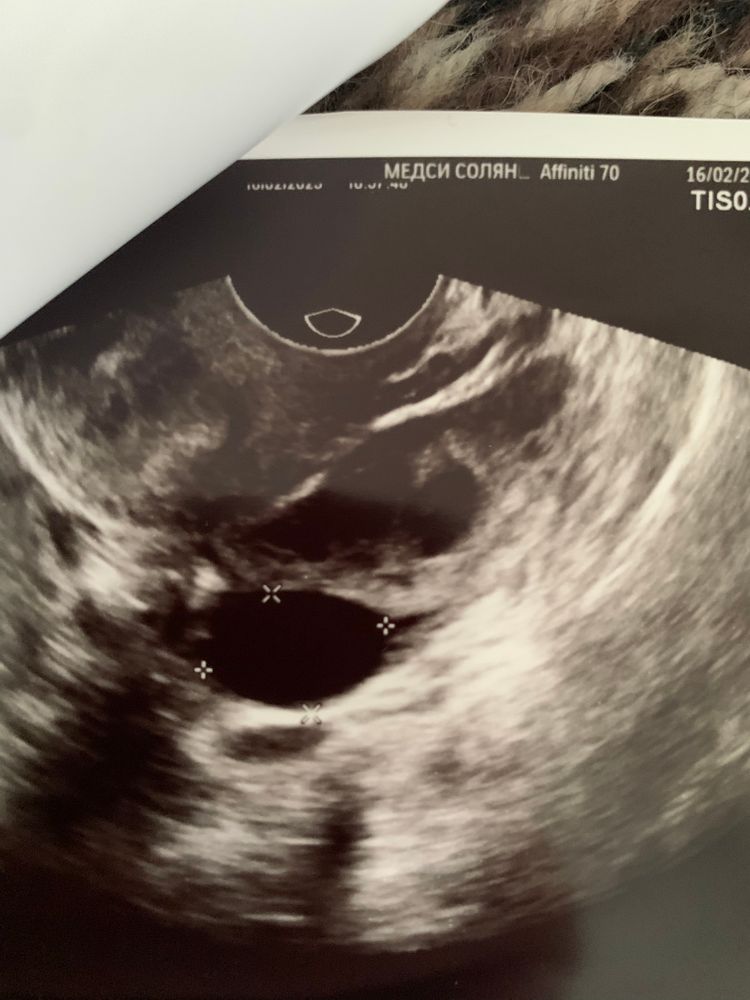

Месячный циклВсем привет! НА узи увидели фолликулярную кисту 2х4 см уже на 8 день цикла. В прошлом цикле пила дюфастон, т.к. на 25 дц еще не было доминантного, специально на узи ходила на 20 и 25, без изменения, хотя на 25 эндометрий почему-то подрос. Мог ли ли на узи в том цикле не заметить растущий фолликул, после чего он из-за дюфастона перерос в кисту? Или это все таки уже в новом цикле фоллик так быстро вырос?

Вероника, знаете, у меня тогда подряд странные циклы были. В этом, когда 2х4 написали справа, мне кажется, что в тот же день все таки была овуляция, цикл был 21 день в итоге. Но в следующем была на 6 дц киста 7см слева. По узи либо напутали первый раз и написали справа, и это выросла та киста, либо после зб и дюфастона организм сошел с ума и начал растить фолликулы как не в себя. Цикл с кистой 7 см длился уже 57 дней, т.е. понадобилось время, чтоб она угасла. В следующем снова овуляция на 8 дц с фолликулом 28х20.

Вероника, Дюфастон пила до короткого цикла. У меня вот эта большая ещё сидит, наверное. На последнем УЗИ на 7 ДЦ уже сомневались киста это или дф, размер 18х10, а в прошлом цикле ее размер последний раз был 20х12. Разница между УЗИ около 3 недель. Либо киста затормозила и почти не уменьшилась, либо реально дф, но эндометрий что-то совсем небольшой был. Написали мне дф, но договорились посмотреть в динамике иначе непонятно. Так что вам бы тоже в динамике посмотреть, я думаю, вполне может быть и дф, и овуляция, они как оказалось не всегда ровные шарики. В прошлом цикле у меня был дф 28х20, и жт такое же.